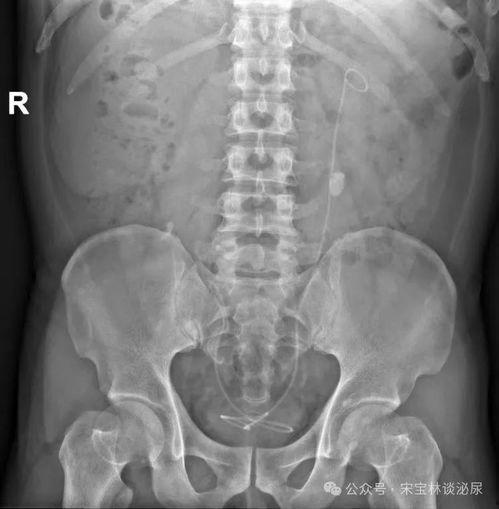

腰椎CT视频,听起来是不是有点高大上?其实,它就是通过CT扫描技术,将腰椎的内部结构清晰地呈现在我们眼前的一种检查方法。那么,它到底能揭示哪些秘密呢?

腰椎间盘突出是导致腰痛的常见原因之一。通过腰椎CT视频,我们可以直观地看到椎间盘是否突出,突出的程度如何,以及是否压迫了神经根。

腰椎管狭窄是指腰椎管内空间变小,压迫神经根或脊髓。腰椎CT视频可以帮助我们判断腰椎管狭窄的程度,为医生制定治疗方案提供依据。

腰椎骨折是老年人常见的疾病,也是导致腰痛的原因之一。腰椎CT视频可以清晰地显示骨折部位、程度以及是否伴有其他并发症。